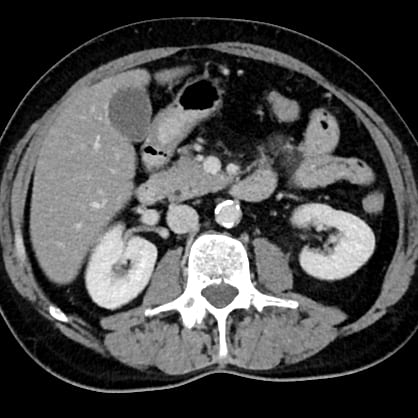

Die Computertomographie (CT) ist ein modernes, schnelles und präzises Bildgebungsverfahren, das mithilfe von Röntgenstrahlen detaillierte Querschnittsbilder des Körpers erzeugt. Besonders gut darstellbar sind hierbei Knochen, innere Organe wie Lunge, Leber und Nieren sowie Blutgefäße. Auch akute Erkrankungen wie Blutungen oder Verletzungen nach Unfällen lassen sich zuverlässig erkennen.